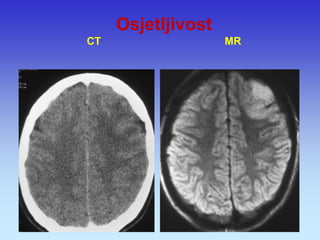

Osjetljivost CT MR